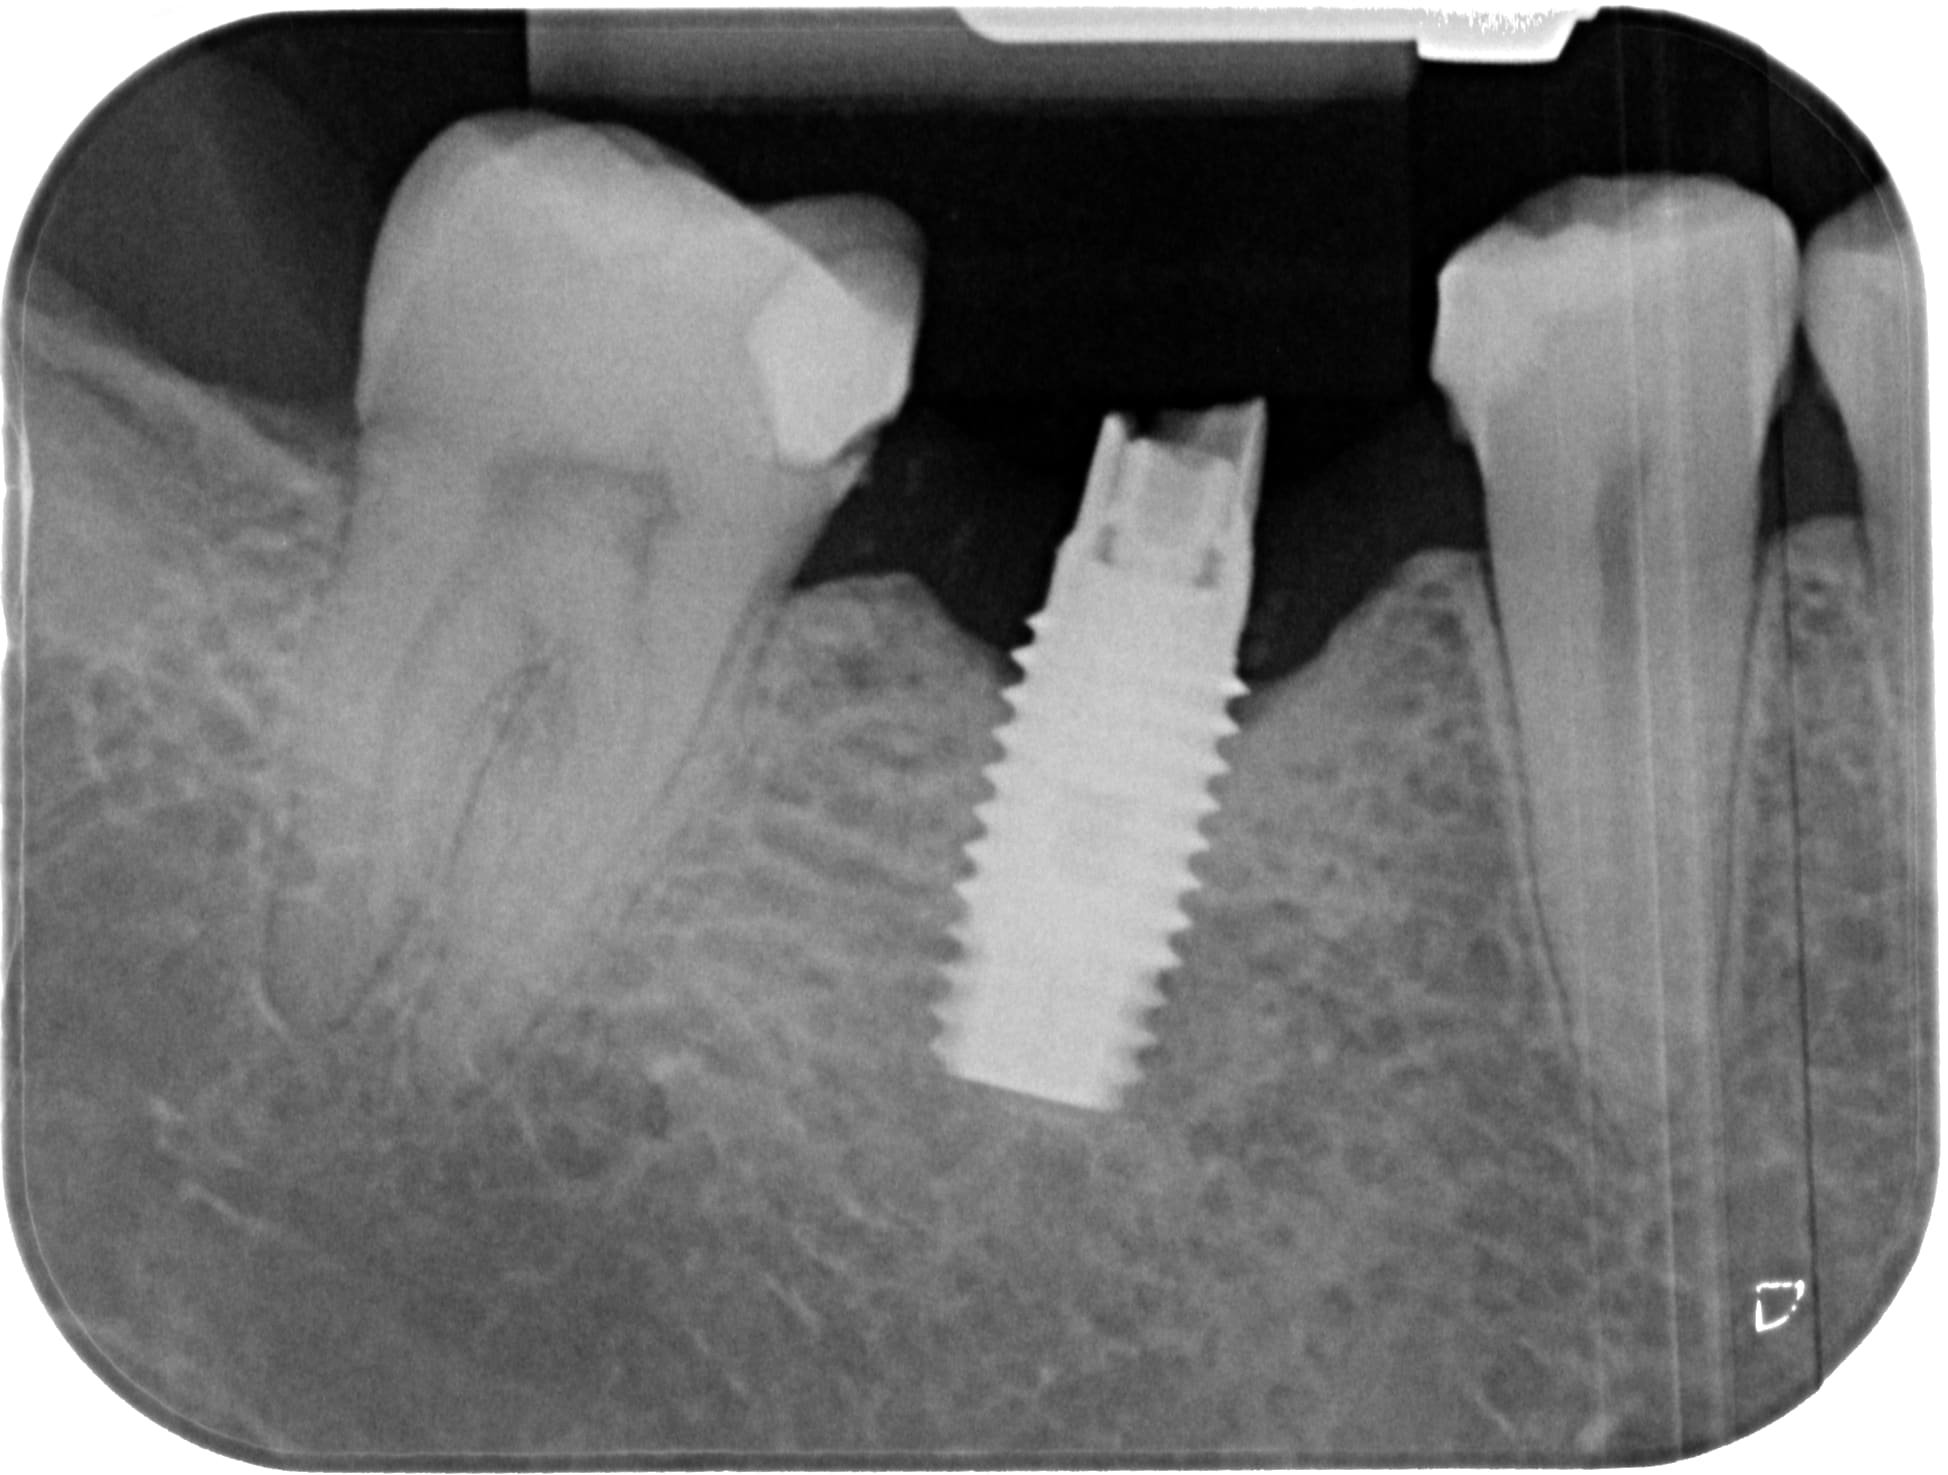

Qui peut m'aider pour la reconnaissance de cette implant?

hexagone externe et tournevis 1.2 compatible ( 1.27 accroche aussi un peu)

Implant posé au COSEM à Paris il y a environ 15 ans.

et la radio sans le pilier toujours pas?